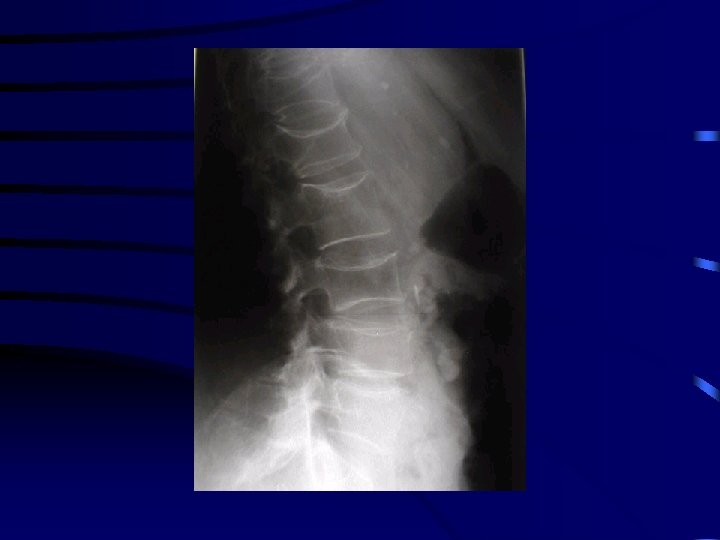

Bilan radiologique • Radiographie 2 incidences • Radiographie du segment Face et Profil • face et ¾ pour les mains et pieds

FRACTURE PATHOLOGIQUE • Survient sur une trame osseuse anormale • souvent traumatisme minime • exemple: ostéoporose kyste osseux